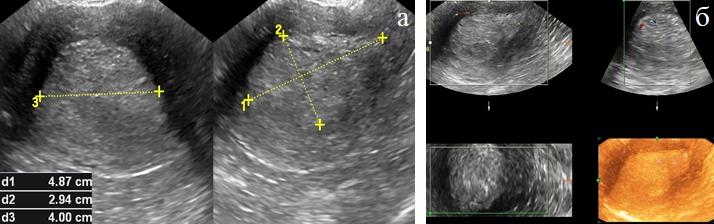

Медицинская диагностика: Гиперплазия эндометрия на УЗИ